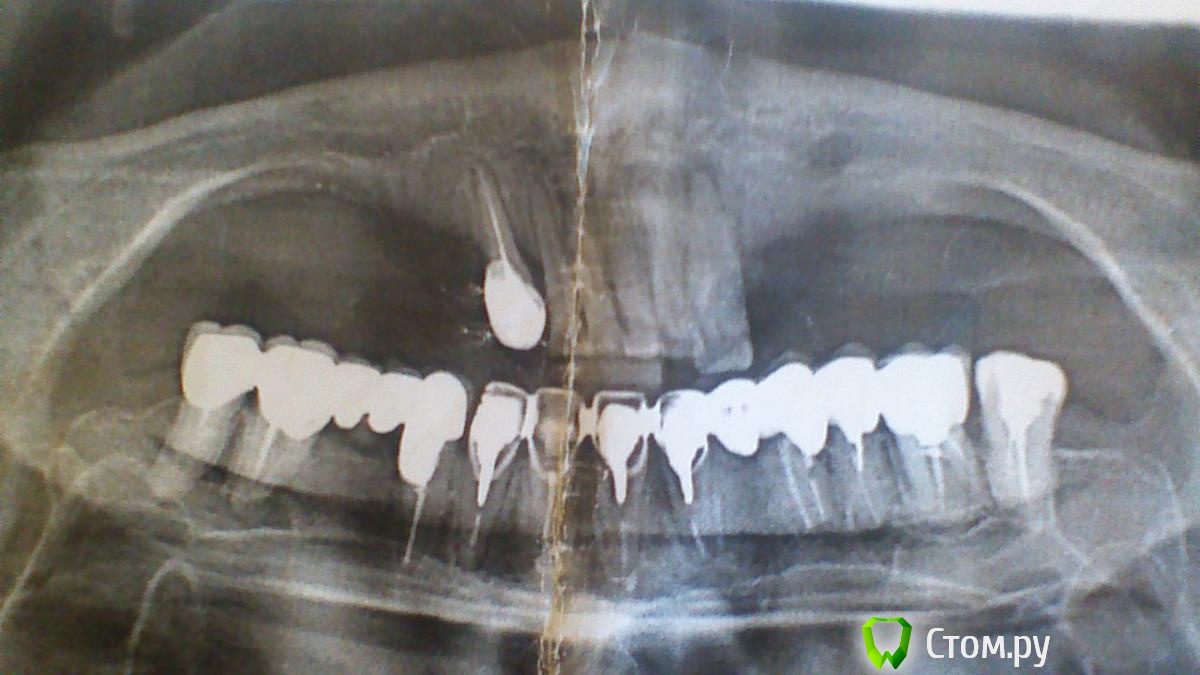

Mancini Опубликовано 2 октября, 2014 Поделиться Опубликовано 2 октября, 2014 (изменено) Здравствуйте, уважаемые стоматологи! Требуется коллективный разум для определения оптимального плана лечения (имплантология) в следующем случае. Дано: Женщина, 61 год, врач (не стоматолог), к.м.н. Все зубы депульпированы. На нижней правой 3-ке киста, которая сейчас находится в процессе пролечивания, результат лечения неопределен (зуб пол временной пломбой). Рот проблемный по крайней мере последние 25 лет, в нем регулярно что-то болит. Зубы и десны болят при малейшем охлаждении (холод, сырость, простуда и т.д.). Имеется остеопороз, парадонтит, дисфункция ВНЧС, компенсированный гипотериоз, низкий болевой порог. Сильно измененный прикус. Присутствуют мышечные спазмы лица, выражающиеся в виде боли, которая переходит с одной четверти рта на другую, потом на третью и четвёртую, далее снова по кругу. Спазмический характер болей предположили в институте стоматологии на ул. Вучетича (Москва), там же категорически отвергли предположение о том, что боли вызваны воспалением тройничного нерва. 3 года назад после удаления нижних 4-ки и 5-ки полгода была на больничном, т.к. раны не заживали, гноились и т.д., после лечения антибиотиками был выявлен кандидоз (брали посев). Последние 3 года имею съемное протезирование на 4-7 зубы нижней челюсти с обеих сторон. Сменила несколько протезов, т.к. они постоянно ломаются. Было 2 нейлоновых протеза – пришли в негодность, сейчас имею пластмассовый, от которого постоянно отлетают крючки. С пластмассовым протезом 1 раз в месяц (!) хожу на перебазировку – по словам врача, уходит десна. В итоге съемными протезами пользуюсь от случая к случаю, что, конечно, ухудшает и без того печальную ситуацию во рту. В настоящее время ищу вариант протезирования нижней челюсти на имплантатах (в 2010 г. в нескольких клиниках почему-то сказали, что импланты невозможны) после полного удаления зубов снизу. Предложено 2 концепции: Удалить все зубы внизу, ждать 2 недели заживления, сделать временный съемный пластмассовый протез, дождаться стабилизации кости после удаления (~ 6 мес.), сделать постоянный съемный пластмассовый протез, начинать обсуждать (только обсуждать!) возможность наращивания кости и последующей имплантации. При неудаче в имплантации – пожизненная съёмная пластмасса. Весь процесс должен занять 1,5 – 2 года. Провести имплантацию в течении 3-4 мес. на следующих условиях: импланты Nobel Replace Groovy в количестве 4 штук устанавливаются одновременно с удалением нижних зубов, при этом импланты ставятся в центральной части челюсти, там где не ушла кость; сразу ставится временная конструкция; постоянное протезирование осуществляется пластиковым протезом на титановой балке Procera (как я поняла, протез как бы условно-съемный), который нуждается в профилактических работах у стоматолога (чистка и прочее) 1 раз в 6 мес. Вторая концепция протезирования предполагает ставить импланты сразу после удаления, не дожидаясь, пока уйдет кость, как это случилось в области 4-7 зубов, где сейчас используется съемный протез. При этом моя ситуация в целом оценивается как обычный штатный случай для имплантации, врач считает, что уходящая кость в районе 5-7 зубов, уходящая десна, из-за которой сейчас ежемесячно перебазируют съемную конструкцию, заживление лунки после удаление в теч 6 мес, имевшее место в прошлом, остеопороз и спазмы не создадут препятствий. Более того, в результате лечения многие эти проблемы должны уйти. В связи с этим прошу ответить на вопросы: Возможно ли протезирование на имплантах в моем случае с учетом состояния кости и уходящих десен по схеме 2-го варианта? Действительно можно обойтись без костной пластики, установив 4 импланта на месте 33-43 зубов? Установка имплантов одновременно с удалением – правильное решение с учетом состояния кости, десны и кисты на правой 3-ке? По вопросу протеза – пластик на титановой пластине будет нормален в эксплуатации, не будет проблем с деснами? Буду признательна за рекомендации врача (врачей) для проведения лечения (в соответствующей теме запрос оставила) и ориентацию по ценам (если возможно). Прилагаю снимки:1. панорамный;2. прицельные зубов нижней челюсти. Заранее спасибо. Изменено 2 октября, 2014 пользователем Mancini Ссылка на комментарий

Mancini Опубликовано 3 октября, 2014 Автор Поделиться Опубликовано 3 октября, 2014 Ваша позиция понятна. Видимо, моих возможностей не хватает для изложения комплексной сложной ситуации в двух предложениях. Переформулирую вопросы, возможно, так будет лучше: 1. Возможно ли протезирование на имплантах в моем случае на нижнюю челюсть (случай представлен на снимках)?2. Требуется ли костная пластика перед установкой имплантов?3. Следует ли соглашаться на установку имплантов непосредственно после удаления зубов нижней челюсти?4. От предложений базальной имплантации следует отказываться сразу?5. Срок службы устанавливаемого на импланты пластикового протеза на титановой балке составляет 2-3 года или другой срок?6. Возможно и разумно ли в данной ситуации, на ваш взгляд, вместо имплантов применить мостовидную конструкцию на 33-43 зубы и съемную на концы? Продолжаю надеяться на компетентные профессиональные мнения по существу ситуации.Буду очень признательна за любые предложения по плану лечения. Ссылка на комментарий

Bier Опубликовано 5 октября, 2014 Поделиться Опубликовано 5 октября, 2014 1. Возможно.2. Либо с транспозицией нерва либо с костной пластикой в боковых отделах, либо по концепции все на 4х, с установкой имплантатов только в переднем отделе н.ч.3. Это возможный вариант, но требует дополнительного обследования (Комп Томография)4. однозначно да.5. Если это условно-съемный протез на балке, то считается, что раз в 3-5 лет пластиковую часть надо менять на новую.6. Съемный всегда хуже несъемного, к тому же он вызовет дополнительную атрофию костной ткани. 1 Ссылка на комментарий